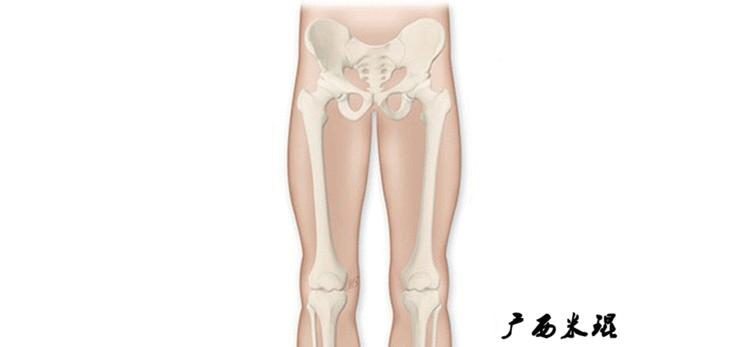

1、确定下肢关节的中心点

(1)髋关节中心

髋关节中心点由股骨头来确定,由于股骨头是相对比较规则的圆形,使用Mose圈或圆规就能确定股骨头中心也就是髋关节中心。

(2)膝关节中心

膝关节中心点常用的有5个不同的定位方法,分别是股骨髁中点、股骨髁间窝顶点、膝关节间隙水平软组织中点、胫骨髁间嵴中点和胫骨平台中点,我们可以根据具体情况来选用。

(3)踝关节中心

踝关节中心点常用的也有3个,分别是骨骼(内、外踝表面间距)中点、踝关节间隙水平软组织中点和距骨宽度中点。

2、画出下肢的轴线

确定髋关节、膝关节、踝关节的中心点后,我们才能了解下肢的几个轴线。